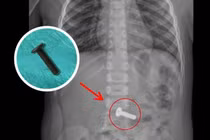

Trẻ 4 tuổi ho và nôn, không ngờ nuốt phải đinh vít hơn 3cm

Khi thấy con ho và nôn, gia đình kiểm tra lại camera thì phát hiện con nuốt một vật nhỏ màu đen rơi ra từ ghế bàn học, đó là chiếc đinh vít.